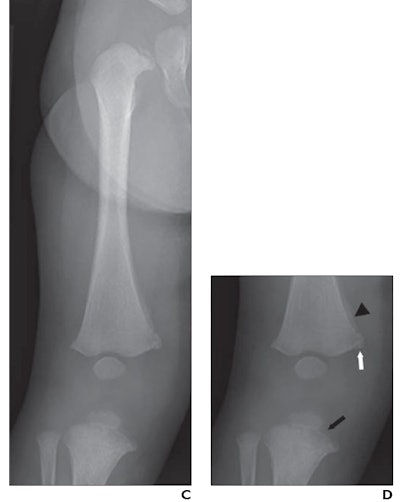

Thus, in this multicenter study, the researchers sought to address the issue by evaluating the diagnostic performance of radiologists in differentiating rickets and CML in children under 2 years old who underwent knee x-rays from January 2017 to December 2018. The children either had rickets (n = 70) or knee CMLs (n = 77) and a diagnosis of child abuse from a child abuse pediatrician.

Images were cropped and zoomed to present similar depictions of the knee, while eight radiologists independently interpreted the x-rays and rated their confidence levels for making diagnoses. Importantly, the radiologists were comprised of both pediatric and nonpediatric specialists with post-training experience ranging from one to 15 years.

According to the findings, the radiologists reached interpretations of rickets and CMLs with substantial to almost perfect agreement. For moderate- or high-confidence interpretations for CML, sensitivity across the eight radiologists was 95.1%, specificity was 97%, and accuracy was 96%.

Other key findings included that children with CML were younger than children with rickets (3.9% vs. 65.7% >1 year old) and that rates of false-positive moderate- or high-confidence interpretations were 0.6% for CML and 1.6% for rickets. Only one child with CML and low vitamin D received an interpretation of combined CML and rickets, the authors found.